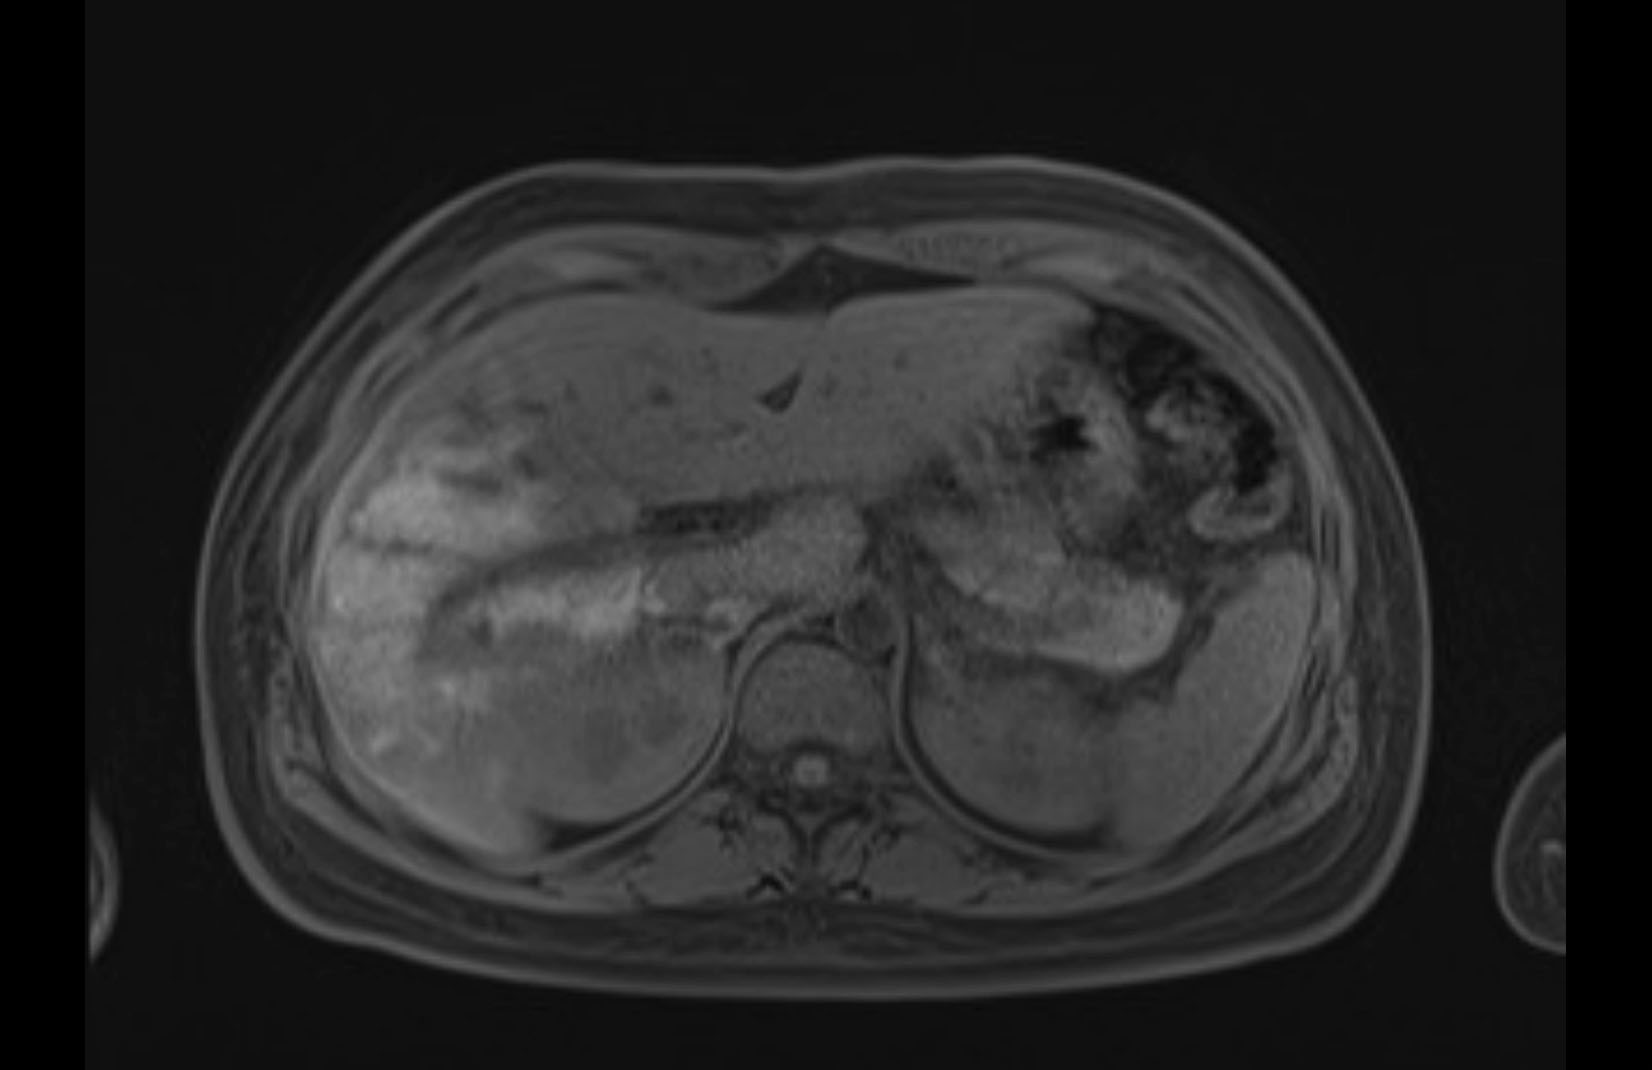

Imaging Analysis

Look through the patient's CT scan to identify any areas of concern for the necessary procedure.

MRI T1

MRI T2

Based on initial findings, which issue(s) would you be most concerned about?